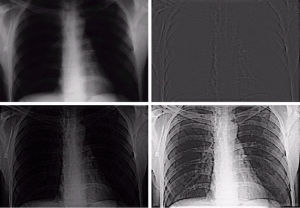

圖像增強技術在生物醫學方面的套用有兩類,其中一類是對生物醫學的顯微光學圖像進行處理和分析,比如對紅細胞、白細胞、細菌、蟲卵的分類計數以及染色體的分析;另一類套用是對X射線圖像的處理,其中最為成功的是計算機斷層成像。1973年英國的EMI公司在製造出第一台X射線斷層成像裝置。由於人體的某些組織,比如心臟、乳腺等軟組織對X射線的衰減變化不大,導致圖像靈敏度不強。由此圖像增強技術在生物醫學圖像中得到廣泛的套用。

圖像增強處理是數字圖像處理的一個重要分支。很多由於場景條件的影響圖像拍攝的視覺效果不佳,這就需要圖像增強技術來改善人的視覺效果,比如突出圖像中目標物體的某些特點、從數字圖像中提取目標物的特徵參數等等,這些都有利於對圖像中目標的識別、跟蹤和理解。圖像增強處理主要內容是突出圖像中感興趣的部分,減弱或去除不需要的信息。這樣使有用信息得到加強,從而得到一種更加實用的圖像或者轉換成一種更適合人或機器進行分析處理的圖像。圖像增強的套用領域也十分廣闊並涉及各種類型的圖像。例如,在軍事套用中,增強紅外圖像提取我方感興趣的敵軍目標;在醫學套用中,增強X射線所拍攝的患者腦部、胸部圖像確定病症的準確位置;在空間套用中,對用太空照相機傳來的月球圖片進行增強處理改善圖像的質量;在農業套用中,增強遙感圖像了解農作物的分布;在交通套用中,對大霧天氣圖像進行增強,加強車牌、路標等重要信息進行識別;在數位相機中,增強彩色圖像可以減少光線不均、顏色失真等造成的圖像退化現象。